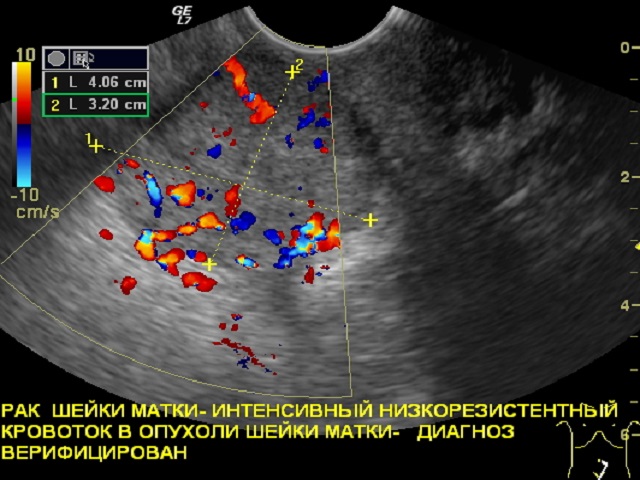

При раке, когда происходит разрастание эндометрия и формируется опухоль, изменяется ультразвуковая проницаемость соответствующей ткани. Поэтому опухоль может быть визуализирована на УЗИ. Эффективность этого метода достаточно высока на средних и поздних стадиях заболевания. Однако на ранних этапах, когда изменения незначительны, признаки онкологического процесса могут быть незаметны. На более поздних стадиях информативность УЗИ достигает 80-90%.

Хотя основным диагностическим признаком остается проницаемость тканей, то есть, контрастность участков изображения, можно рак эндометрия на УЗИ диагностировать и иными способами. Например, в ходе такого исследования можно оценить контуры органа и его полости, состояние полости. Также важную роль играет размер матки, так как при наличии опухоли он, обычно, увеличивается. Если полость расширена, контуры эндометрия и эхогенность изменены, то это говорит в пользу рака.